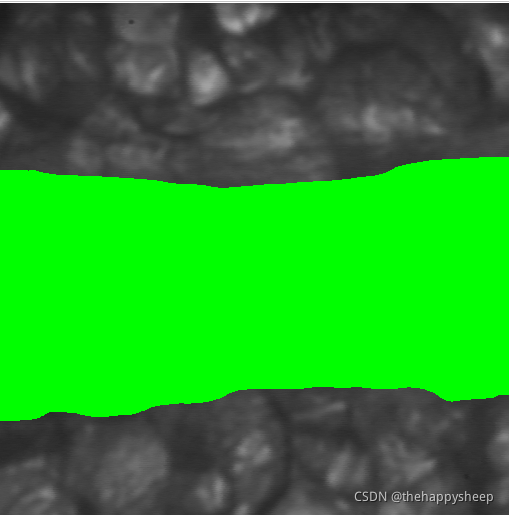

(2)结果图

binary_threshold (Energy, Vessel, 'smooth_histo', 'dark', UsedThreshold)

dev_display (Vessel)

dev_display (Image)

dev_display (Boundaries)

disp_message (WindowID, 'meanDiam: ' + meanDiameter + ', minDiameter: ' + minDiameter, 'image', (UpperRow + LowerRow) / 2, (Width - TxtWidth) / 2, 'yellow', 'false')